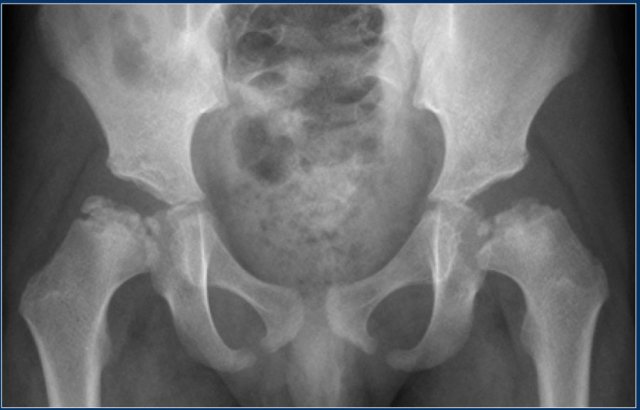

The x-ray is of a 15-year old with acute lymphatic leukemia who was treated with steroids.

The images alone cannot differentiate from Perthes disease, but based on the clinical information, this is secondary avascular necrosis.